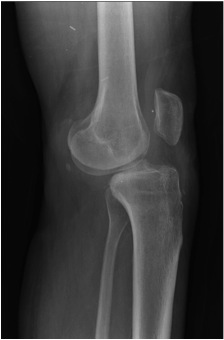

Anterior knee dislocations

Obvious knee dislocation